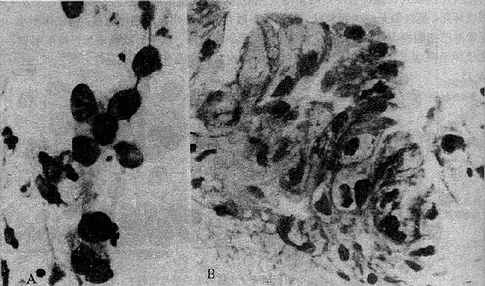

2.上皮细胞持续性放射改变由于放疗后上皮细胞的改变持续时间较长,此时急性放射改变多已不复存在,涂片中可发现核异质细胞,所示胞核增大,染色质呈粗颗粒状,核深染,有时可见核内空泡(图19-12)。胞质呈多色性,有的细胞呈纤维或蝌蚪形。这类核异质细胞需与高分化鳞癌的纤维形或蝌蚪形癌细胞鉴别,其鉴别点为纤维形核异质细胞核虽深染色,有核形不整,但胞核与胞质比例仍在正常范围或略大,其纤维形或蝌蚪形细胞体亦不如癌细胞大。

图19-12 放射治疗后的核异质

子宫颈内膜放疗后6个月的反应,见核增大,有一定程度的染色过深和染色质粗糙

A细胞学涂片 B细胞切片×560